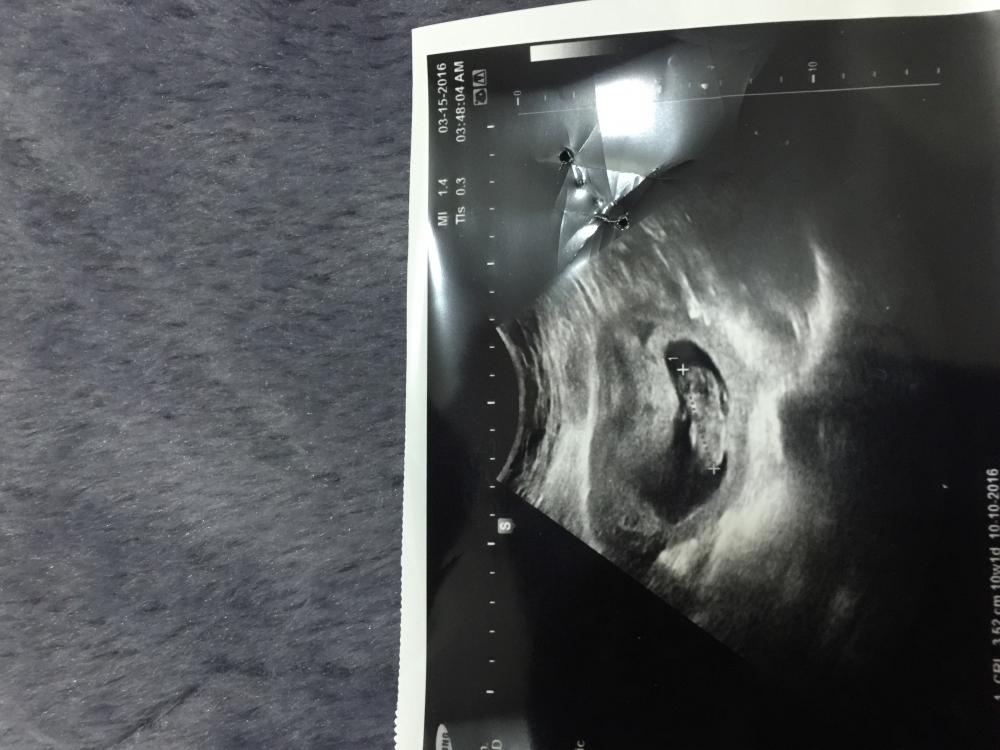

اخت رنا شوفي صوره السونار والله تعبت ع مانزلت اذا مو واضح خبريني لان مدري كيف نزلت السونار ع حساب الدوره اخر اسبوع الثامن وع حساب السونار الاسبوع العاشر ياليت تخبريني وجزاك الله خير